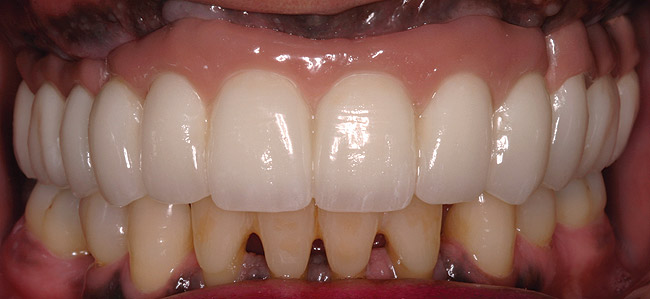

In overdenture therapy, prosthetic design can be divided into two groups: stress-broken and rigid. Stress-broken prostheses require fewer implants, with attention to biomechanical design features to allow for rotation (stress-breaking) of the prostheses around the implant locations. These prostheses are essentially tissue-supported and implant-retained. They replace the adhesive/glue, providing needed retention, comfort, and support. An example would include two implants in site Nos. 23 and 26, with either solitary anchor systems (ball or stud attachments) or a splinted bar-overdenture design (Figure 9 through Figure 11). Masticatory function is improved and patient satisfaction increased. Rigid prostheses require multiple implants, with the forces being transferred from the supra-infrastructure directly to the implants. These prostheses are implant-supported and implant-retained. The design can be removable or fixed (Figure 12 through Figure 16), depending on patient- and operator-mediated preferences.24-27 Within the fixed group of prostheses, materials used may vary from acrylic-fused-to-metal, porcelain-fused-to-metal, or all-ceramic. The cost of these material choices varies significantly, with acrylic options providing the most affordable, entry-level approach for the patient.14